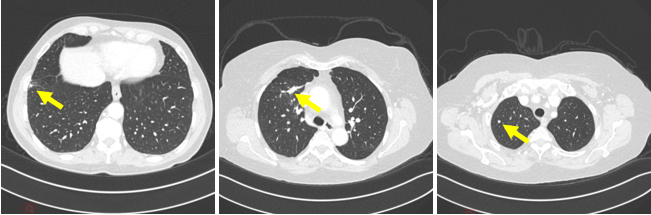

CT成像方式是临床影像诊断的重要手段,计算机辅助诊断系统能够预先标记出病灶位置、病灶类型等基本信息,从而有效缩短放射科医生的阅片时间,提高阅片的准确率。而针对人体肺部等纹理丰富区域进行病灶检测是一个具有挑战性的课题,传统的图像分类方法容易导致误诊和漏诊现象。近年来,深度卷积网络在自然图像分类与检测等领域取得了巨大成功,而医学图像与自然图像统计特征不尽相同。因此,本课题拟将深度学习方法应用到肺部病灶检测领域,对深度网络特征进行深入分析,从而提高肺部病灶检测的准确率,促进计算机辅助诊断系统在肺部疾病诊断中的应用。

交大一附院医生标记的肺部病灶示例